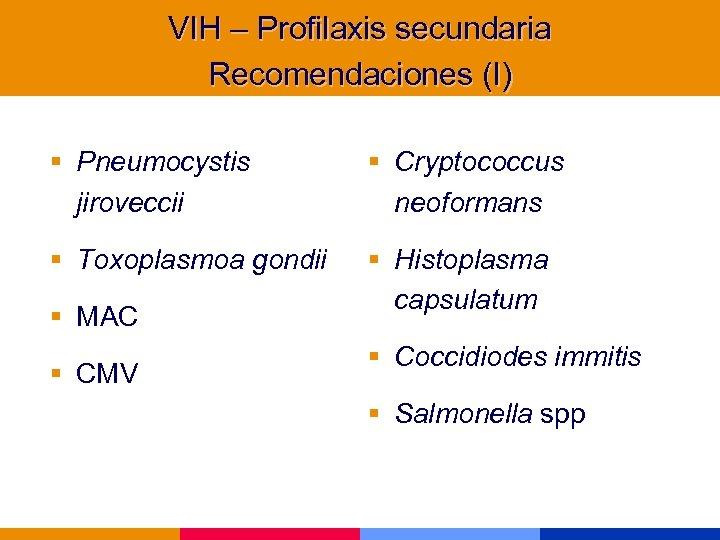

VIH – Profilaxis secundaria Recomendaciones (I) § Pneumocystis jiroveccii § Cryptococcus neoformans § Toxoplasmoa gondii § Histoplasma capsulatum § MAC § CMV § Coccidiodes immitis § Salmonella spp

VIH – Profilaxis secundaria Recomendaciones (I) § Pneumocystis jiroveccii § Cryptococcus neoformans § Toxoplasmoa gondii § Histoplasma capsulatum § MAC § CMV § Coccidiodes immitis § Salmonella spp